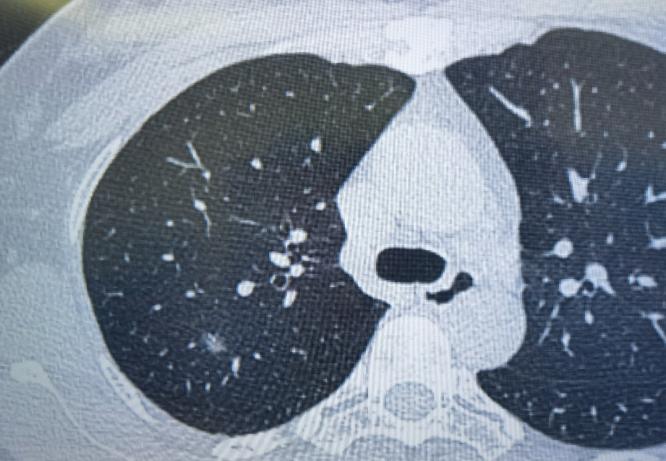

这位33岁的女性患者,体检发现右肺有2个磨玻璃结节,可以清楚地看到,这两个结节与